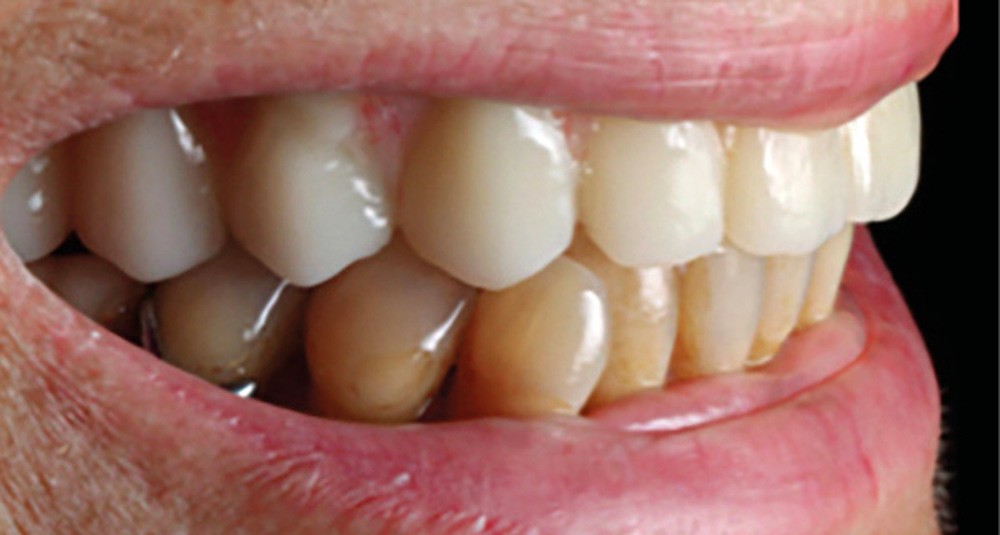

Après une extraction atraumatique des dents résiduelles, nous passons au 3e étage qui est le guide de forage stéréolithographique. La séquence de chirurgie Full guided est passée et les implants ont été torqués entre 40 et 50N.cm2 (fig. 6, 7, 8). Cette stabilité primaire dans les sites d’extraction et des sites greffés a permis la mise en charge immédiate du bridge complet provisoire. Des études cliniques [3, 4, 5] ont montré que la mise en charge immédiate dans les sinus greffés ne pose aucune contre-indication. Le 4e étage est donc celui du bridge provisoire transvissé à l’étage de base et solidarisé en bouche par l’intermédiaire de cylindres provisoires sur piliers MUA, avec une colle duale (GC-LinkForce). L’espace entre les implants et l’alvéole a été comblé par une xénogreffe (Bio-Oss Geistlich). Les profils d’émergence sont travaillés et parfaitement polis. Enfin, le bridge est mis en place, torqué à 20.cm2, équilibré et les consignes postopératoires ont été rappelées à la patiente (fig. 9 et 10).

Notre approche globale dans la gestion de ce cas clinique avec l’aide du flux numérique et l’utilisation des guides à étages nous a permis de traiter cette patiente avec succès, sérénité et de rendre son traitement prévisible.